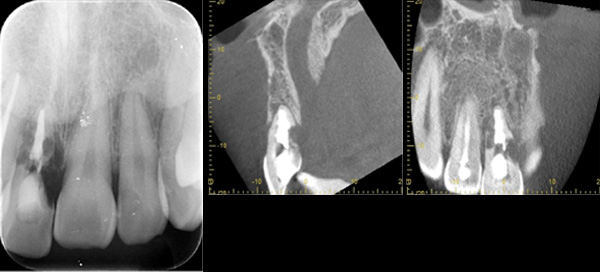

| 年代・性別 | 30代 男性 |

|---|---|

| 主訴 | 前歯が腫れた |

| 治療期間 | 約18ヶ月 |

| 費用 | 700,000円 |

| 治療内容 | インプラント、部分矯正、骨造成、結合組織移植、セラミック修復 |

| 治療に伴うリスク | インプラント周囲炎 セラミックの破折、脱離 |